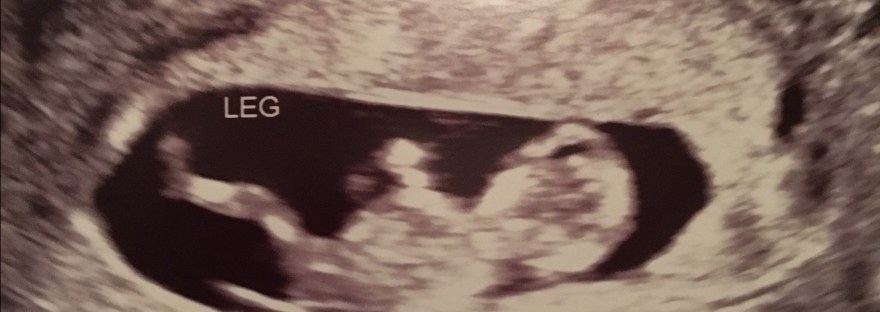

So, it's been a little while, and in case you haven't heard yet- Will and I are finally expecting a baby again! However, this time we have finally made it to 16+ weeks (WHICH IS SO EXCITING!)  The picture above is from a little over 11 weeks- we'll get some new glamour shots on Friday!… Continue reading Baby Cashion: Boy or Girl-the current debate!